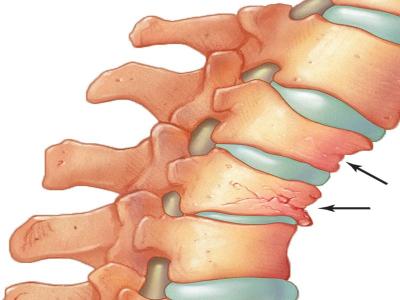

ऑस्टियोपोरोसिस हड्डी का चयापचय रोग है, जो हड्डियों के घनत्व में कमी से होता है। आसान भाषा में कहें, तो एक ऐसी समस्या है, जिसमें कैल्शियम की कमी के कारण हमारी हड्डियां कमजोर होने लगती हैं। इस रोग में हड्डियों के फ्रैक्चर का अधिक खतरा होता है।

डब्ल्यूएचओ की हालिया रिपोर्ट के अनुसार हार्ट डिजीज के बाद ऑस्टियोपोरोसिस विश्व की दूसरी सबसे ज्यादा प्रभावित करने वाली बीमारी है। दुर्भाग्यवश इस रोग के शुरूआती संकेत और लक्षण दिखाई नहीं देते हैं और मरीज की 'बोन मास' व 'बोन टिश्यू' (जो हड्डियों की ताकत होती है) का निरंतर ह्रास होता है।

इस वजह से धीरे-धीरे हड्डियां कमजोर और खोखली होती चली जाती हैं। आजकल यह समस्या बहुत आम हो गई है। कम उम्र के युवा भी इसके चपेट में आ रहे हैं और इसकी सबसे बड़ी वजह खराब खानपान और खराब जीवनशैली है।